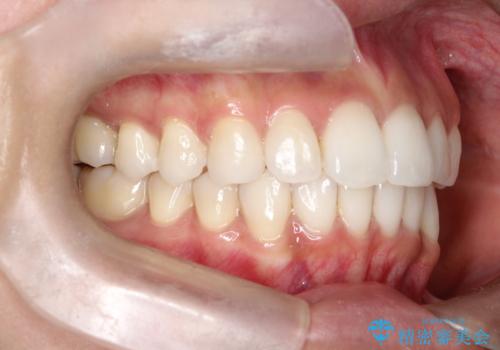

【インビザライン】前歯の凸凹をIPRで改善

- 前歯の凸凹を主訴に来院されました。

前歯を並べるために歯と歯の間にヤスリを入れてわずかに歯を削ることでスペースを確保しています。

歯と歯の間にヤスリを入れてわずかに歯を削ることでスペースを確保する処置をIPRと呼びます。

当院では拡大鏡を用いて丁寧に処置することで歯冠形態を損なわずに行うことができます。